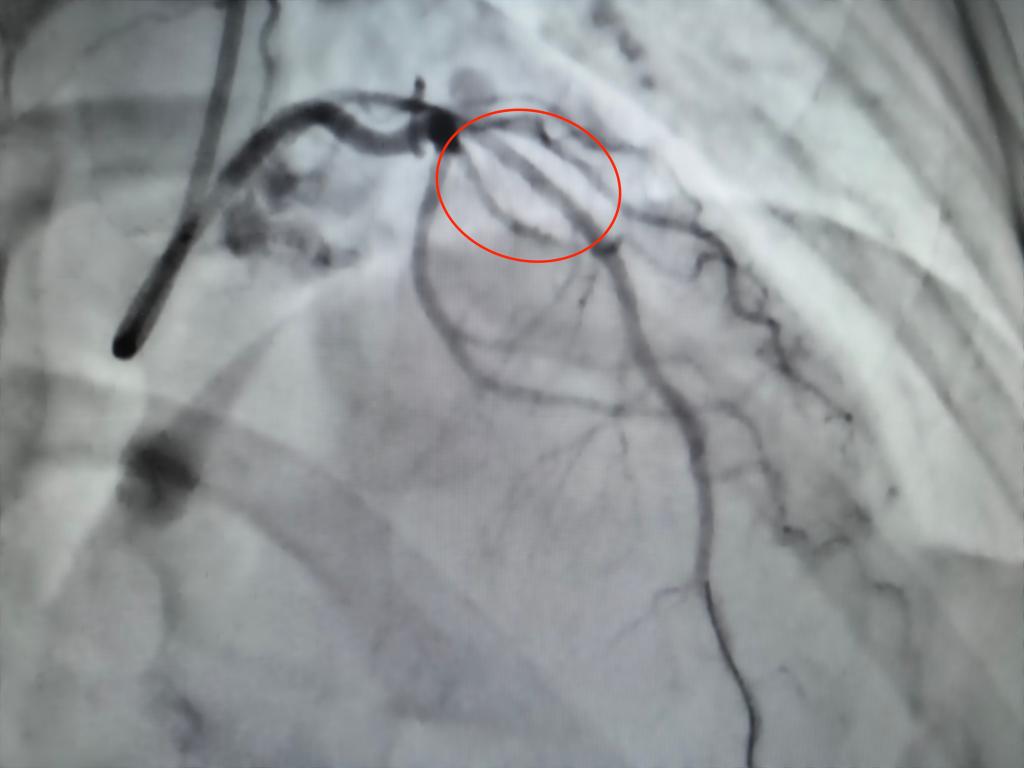

2026年3月20日,在我院心脏介入团队杨凤鸣副主任、曹程浩副主任医师的精心操作下,患者的冠脉药物球囊扩张术顺利完成。术后进行的造影结果显示,原本前降支血管95%的狭窄成功解除,血流恢复通畅状态。目前,患者的生命体征平稳,为她在近期内安全地进行卵巢肿瘤手术奠定了坚实的基础。